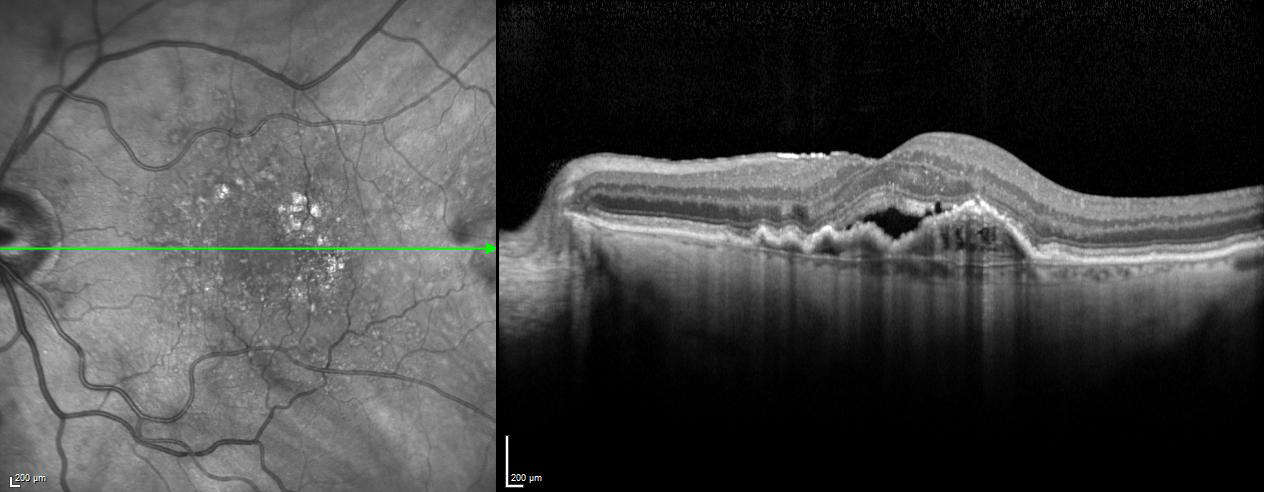

EDI – Enhanced Depth Imaging Mode

The Enhanced Depth Imaging Mode (EDI) of the SPECTRALIS is an OCT imaging technology that enables better visualization of choroidal vasculature. By automatically inverting the image and leveraging the benefits of technologies like TruTrack Active Eye Tracking and Noise Reduction, SPECTRALIS delivers superior images to depict the choroid, allowing to manually measure choroidal thickness.

Semi‐Automated Quantification of Retinal and Choroidal Biomarkers in Retinal Vascular Diseases: Agreement of Spectral‐Domain Optical Coherence Tomography with and without Enhanced Depth Imaging Mode